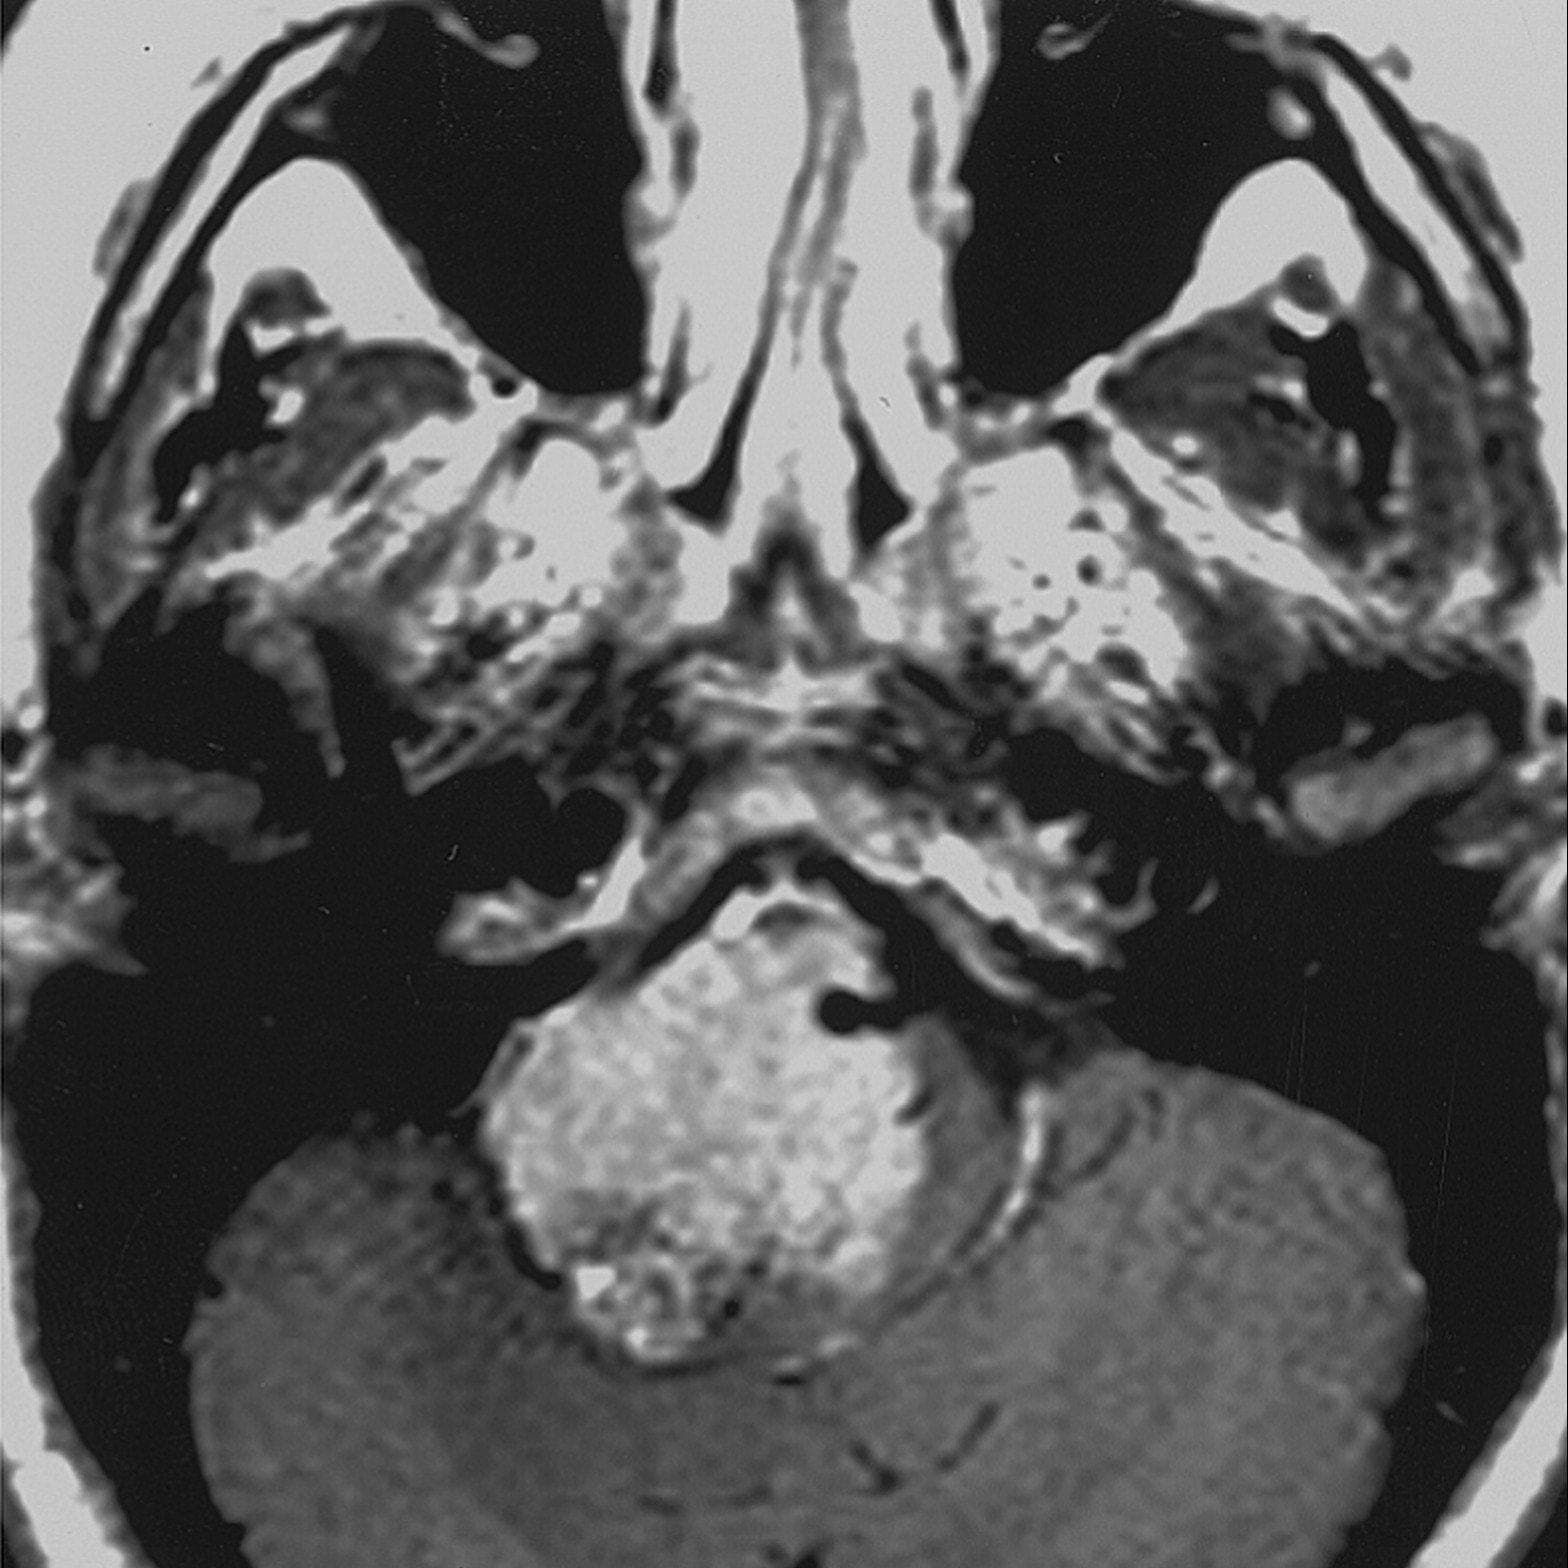

Possible symptoms of cervical degenerative disc disease include radiating pain in the shoulders, arms, and hands. I'm assuming you are referring to peripheral nerve. Degenerative disease is the result of a continuous process based on degenerative cell changes, affecting tissues or organs, which will increasingly deteriorate over time. Degenerative brain diseases are caused by the decline and death of nerve cells called neurons. Degenerative disorder of motor neurons in the spinal cord and brainstem.

Degenerative brain diseases are caused by the decline and death of nerve cells called neurons. I am unaware of degenerative nerve disease. Patients with this disorder have a rapid deterioration of. What are the concerns with having degenerative nerve diseases? answered by dr. Social security disability and ssi for degenerative disc disease can awarded through a disability listing or by a medical vocational allowance approval. The peripheral nerves are frequently compromised due to degenerative disc and facet disease in the spine. Degenerative neurological and neuromuscular disease vols. Motor neurone disease (mnd) is a rapidly progressing, neurological disease.

This arrangement admits the application of diffusion tensor imaging, a. Increasingly, degenerative disc disease is viewed differently from the normal process of degeneration associated with aging. Most of them have no cure. Degenerative nerve diseases affect many of your body's activities, such as balance, movement, talking, breathing, and heart function. This consists of all other neural elements, including the peripheral nerves and the autonomic nerves. Alphabetical list of currently known human neurological conditions including short neurological disorders affect the brain as well as the nerves found throughout the human body and a rare degenerative disease of the brain involving the grey matter. A chronic autoimmune disease that affects the neuromuscular junction and produces serious weakness of voluntary muscles. Motor neurone disease (mnd) is a rapidly progressing, neurological disease. Neurodegenerative disease processes lead to the destruction of normally functioning neurons and their replacement by functionally definition wallerian degeneration refers to the secondary antegrade degeneration of the axon and myelin sheath distal to the level at which the. Visit clinicaltrials.gov for a list of ongoing clinical trials. The peripheral nerves are frequently compromised due to degenerative disc and facet disease in the spine. Degenerative brain diseases are caused by the decline and death of nerve cells called neurons. Pain that radiates down the leg is a symptom of sciatica.

See a list of all the diseases. Degenerative brain diseases are caused by the decline and death of nerve cells called neurons. Degenerative nerve diseases cause worsening of many of your body's activities, including balance, movement, talking, breathing and heart function. Find out information about degenerative nerve disease. Motor neurones are nerve cells that control the voluntary muscles of the trunk and limbs, and affect speech. It is characterized by acute onset. This consists of all other neural elements, including the peripheral nerves and the autonomic nerves. Possible symptoms of cervical degenerative disc disease include radiating pain in the shoulders, arms, and hands. It depends on the type. Degenerative neurological and neuromuscular disease vols. Mrs fletcher, who has a daughter megan, 13, suffers from a degenerative nerve disease and has been confined to a wheelchair for 11 years. Spinal disks are like shock absorbers between the the stress of everyday movements and minor injuries over the years can cause tiny tears in the outer wall, which contains nerves. In the central and peripheral nervous systems, most axons over a critical diameter are enwrapped by myelin, which reduces internodal membrane within a tract or nerve, axons are packed densely and (in general) aligned in parallel.